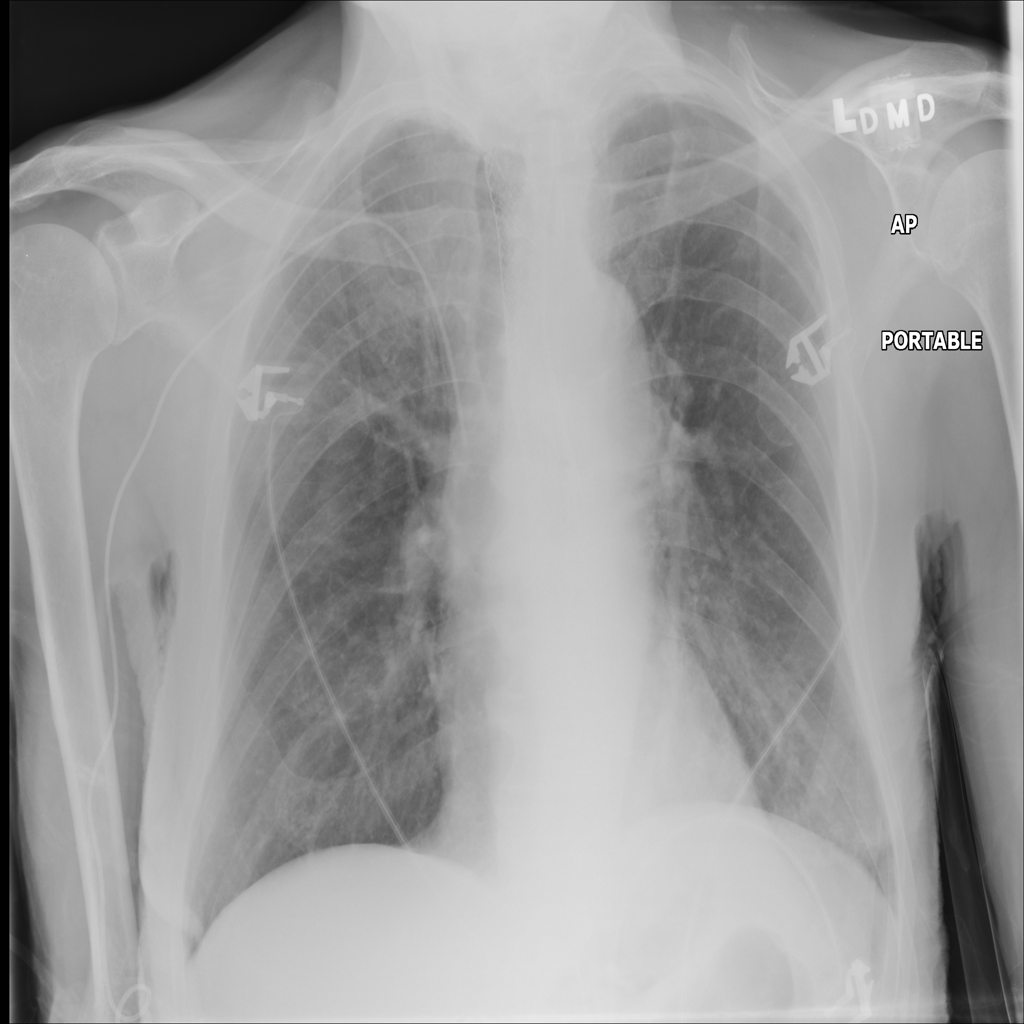

PAT-D3CD · IMG-009Pneumonia

PAT-D3CD · IMG-009

PA